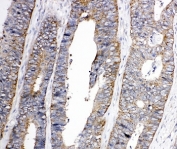

IHC-P: EphA1 antibody testing of human colon cancer tissue. HIER: steamed with pH6 citrate buffer.